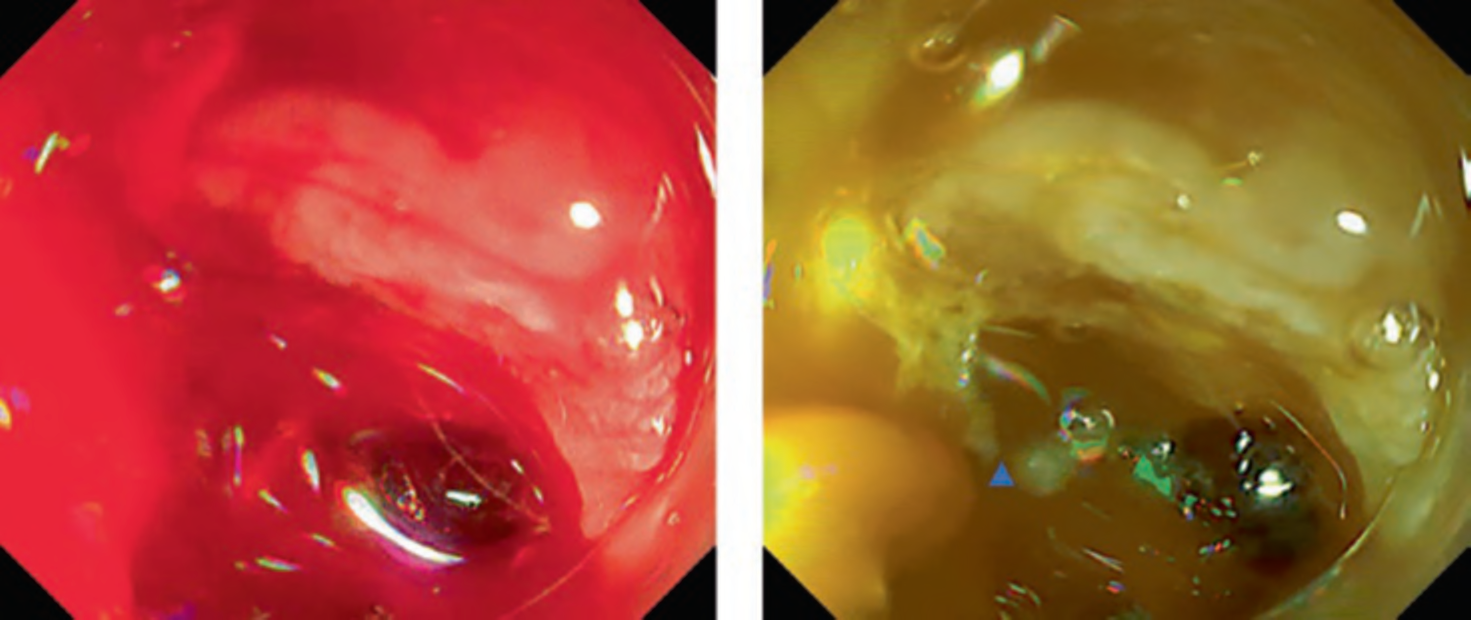

This mode is mainly aiming for identification of bleeding points. In cases of active bleeding, it is often difficult to continue the hemostasis because the pooled blood disturbs visualization. Potential usefulness of RDI in ESD by the improvement of identification of bleeding point has been reported [2–4]. A multicenter randomized controlled trial revealed significant reduction of endoscopists’ psychological stress during hemostasis even though it failed to show the shortening of hemostasis time [5]. There is also a case report of successful hemostasis for active bleeding due to peptic gastric ulcer [6] (Figs. 3, 4, and 5).

Fig. 3 Figure of oozing bleeding in gastric endoscopic mucosal resection. a White light imaging. b RDI mode 1

Fig. 4 Figure of spurting bleeding in duodenal ulcer. a White light imaging. b RDI mode 1

Fig. 5 Figure of spurting bleeding during duodenal endoscopic submucosal dissection. a White light imaging. b RDI mode 1